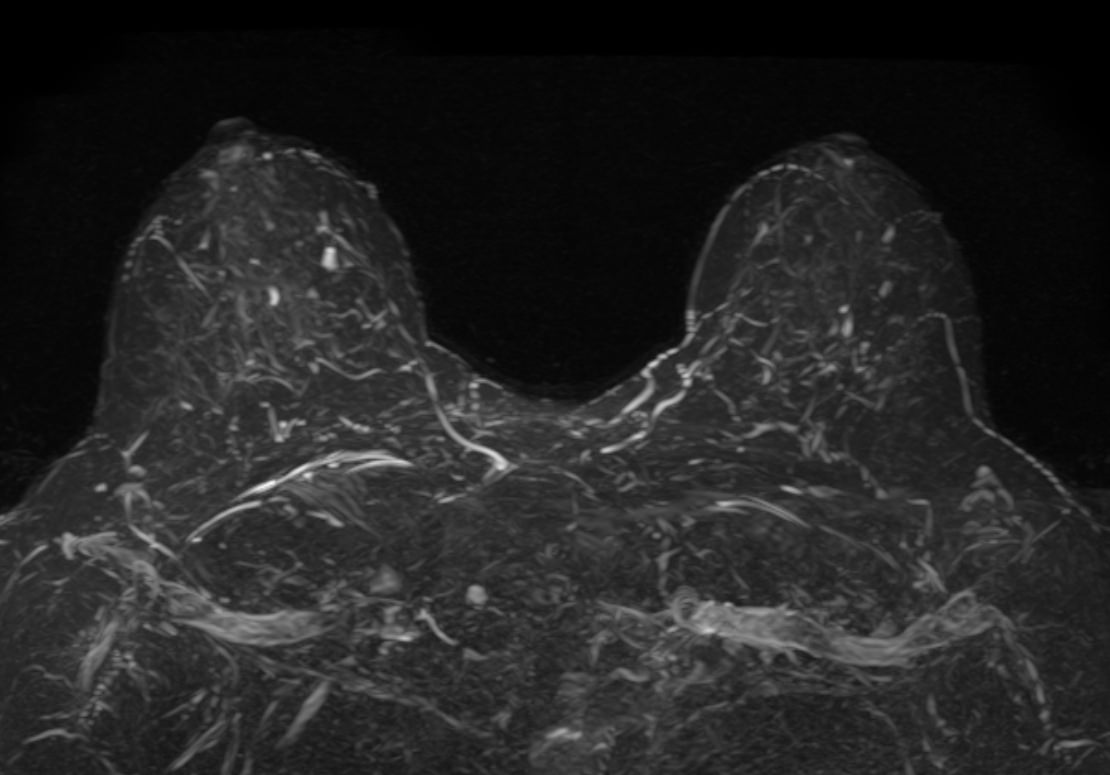

МРТ молочных желез является наиболее точным методом исследования для диагностики заболеваний груди у женщин, и в первую очередь, злокачественных новообразований. Это позволяет выявлять патологические процессы на самых ранних стадиях развития и назначать своевременное лечение, что в конечном счете, может сохранить жизнь и здоровье пациента.

Выполнение МРТ молочных желез без контрастирования возможно для динамического наблюдения состояния имплантатов после пластической операции груди. Во всех остальных случаях во время проведения исследования внутривенно вводится контрастное вещество. Для контрастного усиления применяются препараты на основе солей гадолиния (Магневист, Гадовист и др).

Полученные во время исследования результаты сканирования при помощи компьютерной программы преобразуются в 3D-изображения, что дает детальную информацию о состоянии молочных желез и регионарных лимфоузлов.